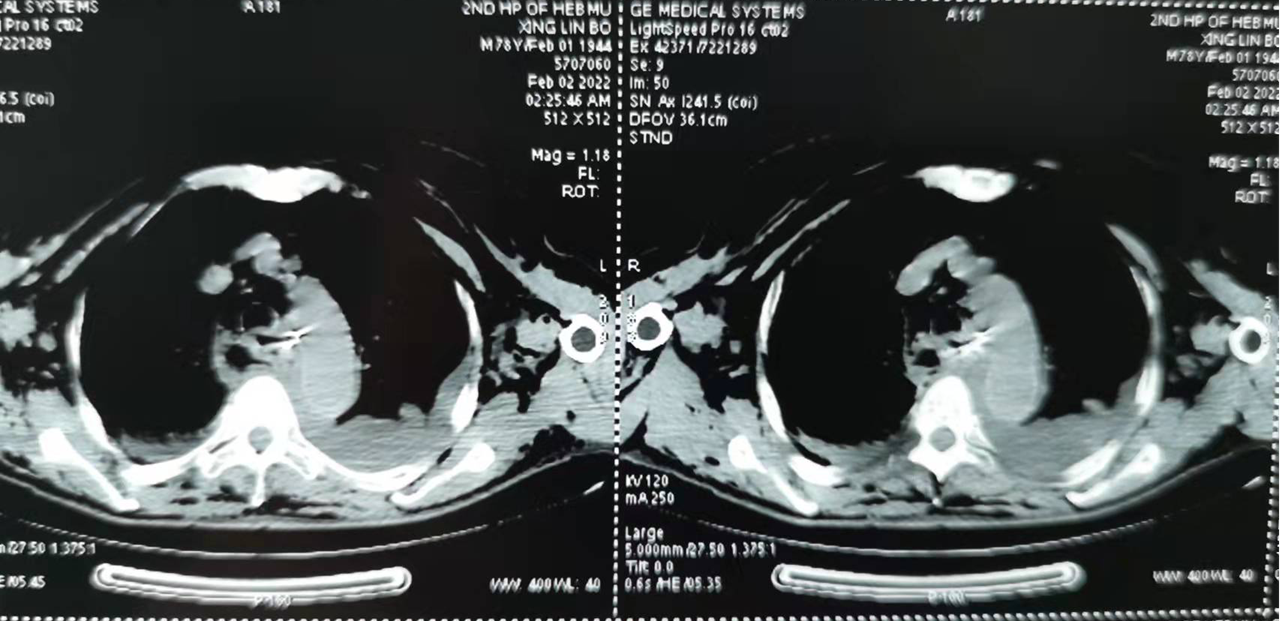

我院成功救治一例高龄食管异物穿孔并纵隔感染患者

我院成功救治一例高龄食管异物穿孔并纵隔感染患者 关键字:胸外科 近日,我院胸外科与消化内科、麻醉科、手术室、急诊ICU精诚合作,成功治疗一例食管异物伴感染,同时合并...